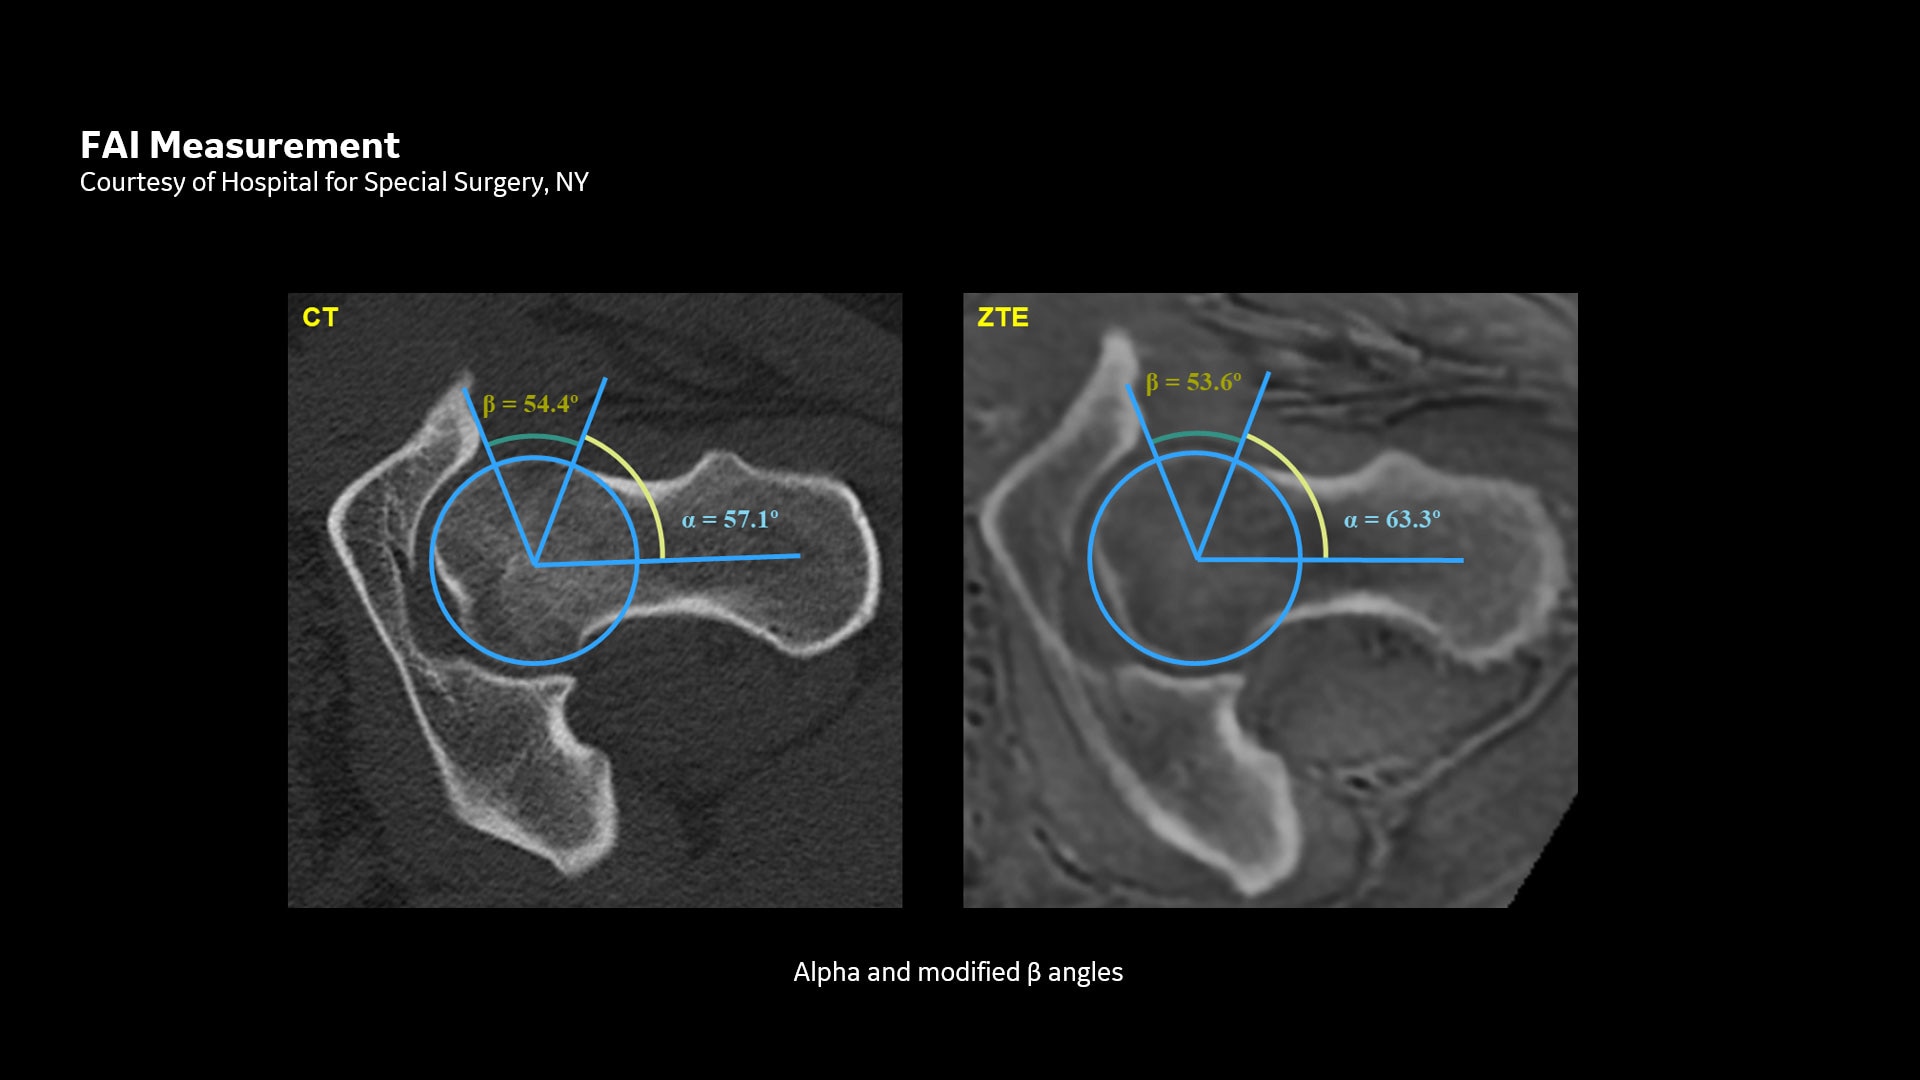

oZTEo für die MRT-Knochenbildgebung

Erweitern Sie mit oZTEo Ihre MSK-Bildgebung zur MR-Knochenbildgebung. Dies bietet Ihnen neue Möglichkeiten für die Orthopädie.

Mit dieser neuen Anwendung zur Darstellung von kortikalen Knochenoberflächen, basierend auf der radialen ZTE-Anwendung, können Sie eine neue Möglichkeit für die Knochenbildgebung anbieten und einen erheblichen klinischen Nutzen für Ihre orthopädischen Untersuchungen gewinnen.

oZTEo ist für alle Anatomien ohne ionisierende Strahlung verfügbar und liefert dabei Bilder von Knochenmorphologie, Verkalkungen, Verknöcherungen und Frakturen. OZTEo ergänzt die herkömmliche MRT-Weichteilgewebeuntersuchung mit perfekter Anpassung und bietet isotropische 3D-Bildgebung unter Verwendung einer radialen ZTE-Erfassung (Zero TE) mit inhärenter Unempfindlichkeit bei Bewegungen. Verwendung von oZTEo mit Volumenbeleuchtung für realistisches 3D-Rendering.